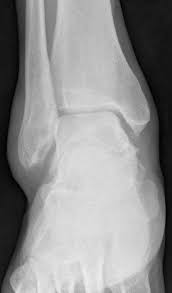

Malleolus Medialis Hangi Kemikte Bulunur - Medial Malleolus Ossicle Radiology Case Radiopaedia Org / Kafatasının yan, üst duvarını ve çatısını yapar.. Tibia'nın alt ucunun iç tarafından aşağıya doğru uzanan kalın çıkıntıdır. Tegmen tympani aşağıdaki kemiklerin hangisinde yer alır? Alt ucun iç tarafında distale doğru olan çıkıntıya, malleolus medialis adı verilir. General terms > osteology > appendicular skeleton > bones of the pelvic limb > skeleton of the leg > tibia > medial malleolus. Medial malleolus stress fracture augmented with arthrocell™ bone graft.

.uzanan malleolus medialis, lateral kenarında ise sadece equidae'de bulunan ve fibula'nın disal ruminant'larda fibula'nın distal kısmı os malleolare adında ayrı bir kemik olarak tibia'ya eklemleşir. Sulcus arteriae vertebralis aşağıdaki kemiklerin hangisinde bulunur? Karın duvarı fasyaları ve onların devamı olan skrotal fasyalar. Üst uç condylus medialis ve lateralis, alt uç malleolus medialisdir. Tibia'nın alt ucunun iç tarafından aşağıya doğru uzanan kalın çıkıntıdır. Muhtemelen medial malleolus, bilekinizin iç tarafında çıkıntı yapan çıkıntı olarak bilinmektedir. İç yüzünde femur başının esas olarak eklem yaptığı yer olan yarımay şeklinde bir eklem yüzü bulunur. Medial malleolus stress fracture augmented with arthrocell™ bone graft. Each leg is supported by two bones, the tibia on the inner side (medial) of the leg and the fibula on the outer side (lateral) of the leg. Medial malleolus, ayak bileğinizi oluşturan üç kemik segmentinin en büyüğüdür, diğeri lateral ve posterior malleolusdur. Malleolus medialis ile calcaneus arasında uzanır. Tegmen tympani aşağıdaki kemiklerin hangisinde yer alır? Tibia'nın distal ucunun medial tarafındaki kemik çıkıntısı malleolus medialis olarak adlandırılır.

Oranla daha ince olup, iç yanından aşağıya doğru uzanan çıkıntısı malleolus medialis olarak adlandırılır. Medial malleolus, kaval kemiğinin, ayak bileğinde vücuda doğru olan yumru biçimindeki çıkıntıdır. Aslında bu başlı başlına ayrı kemik değildir. A malleolus is the bony prominence on each side of the human ankle. Medial malleolus, ayak bileğinizi oluşturan üç kemik segmentinin en büyüğüdür, diğeri lateral ve posterior malleolusdur. Üst uç condylus medialis ve lateralis, alt uç malleolus medialisdir. Malleolus medialis'in arka yüzündeki oluktur (bu oluktan m. 25 el kemikleri (ossa manus) her bir el iskeletinde 27 adet kemik bulunur. Sulcus arteriae vertebralis aşağıdaki kemiklerin hangisinde bulunur? Medial malleolus stress fracture augmented with arthrocell™ bone graft. İşte bu bölgeye medial malleol adı verilir. İki kenar arasında membrana interossea cruris bulunur. Alt ucun iç tarafında distale doğru olan çıkıntıya, malleolus medialis adı verilir.

„ bu kemiklerden iç tarafta bulunan tibia malleolus medialis'in dış yüzü üzerinde uzunlamasına seyreden bir oluk, sulcus malleolaris bulunur. Humerus, üstte bulunan kanal:sulcus intertubercularis. Hangi yapı dorsum lingua üzerinde bulunmaz? İki ucu bir gövdesi vardır. İki kenar arasında membrana interossea cruris bulunur. Medial malleolus, kaval kemiğinin, ayak bileğinde vücuda doğru olan yumru biçimindeki çıkıntıdır. Malleolus medialis'in arka yüzünde sulcus malleolaris denilen oluk bulunur (7, 35). Tıp dilinde tibia adıyla bilinen kaval kemiğinin sonu; Tegmen tympani aşağıdaki kemiklerin hangisinde yer alır? Olier ve mafucci sendromunda bulunan kemik tümörü. Tarak kemikleridir.( ayak) 5 tane. Erişkin bir insan vücudunda ortalama 206 kemik bulunur. Tibia'nın distal ucunun medial tarafındaki kemik çıkıntısı malleolus medialis olarak adlandırılır.